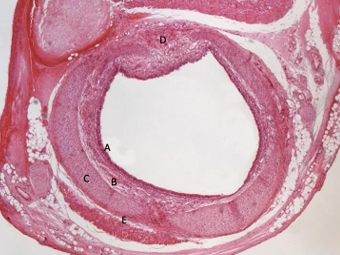

aorta nr 455

= tętnica typu sprężystego

śródbłonek = endotelium

warstwa wewnętrzna

warstwa środkowa: błona środkowa z włóknami sprężystymi i mięśniowymi gładkimi

blaszka sprężysta wewnętrzna i zewnętrzna

przydanka (tkanka łączna)- warstwa zewnętrzna naczyniami naczyń krwionośnych